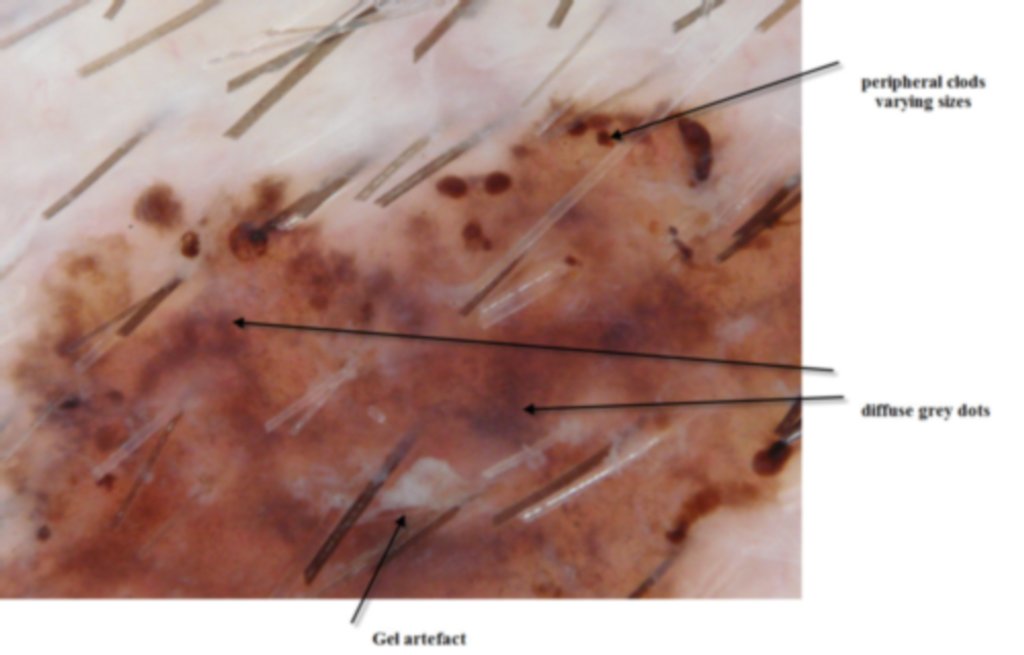

This lesion was noted fotuitously when the patient was having another procedure done on his back. Dermatoscopically it shows peripheral clods of varying sizes, multiple colours and on the enlarged dermatoscopic view some diffuse fine grey dots. It was an invasive melanoma Level 2 , 0.4mm in depth . The histology shows an unusual feature of acantholysis of the tumour nests.